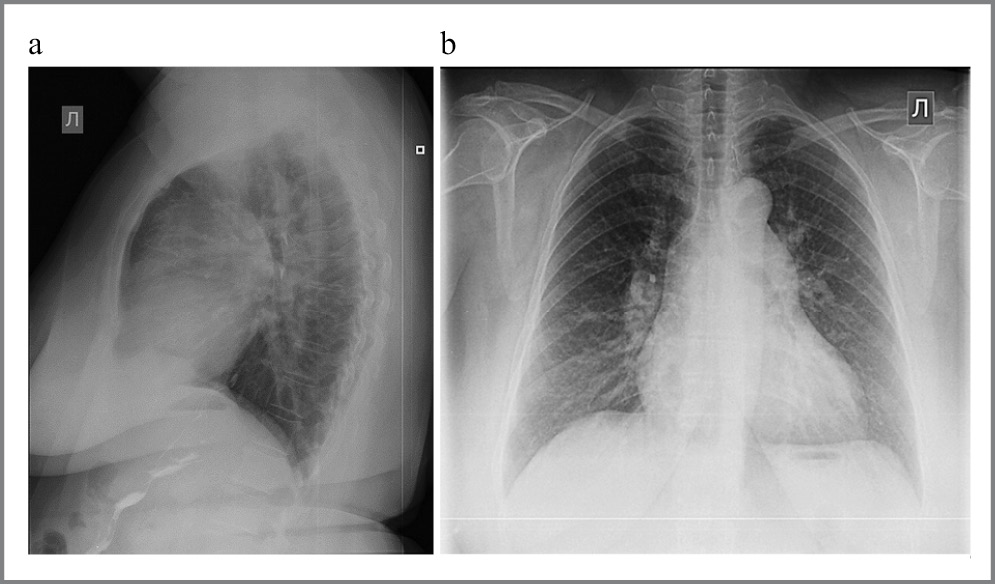

По данным проведенной рентгенографии органов грудой клетки выявлены увеличение правых отделов сердца и высокая артериальная легочная гипертензия [коэффициент Мура – 7,5 мм (при норме от 0 до 1 мм), коэффициент Люпи – 39% (норма до 33%), нисходящая ветвь правой ЛА 21 мм (норма <15 мм), левая ЛА – 31 мм (норма <24 мм)]; рис. 5.

Рис. 5. Рентгенография органов грудной клетки больной: а – левая боковая проекция; b – прямая проекция. / Fig. 5. X-ray of the patient's chest: a – left lateral projection; b – direct projection.